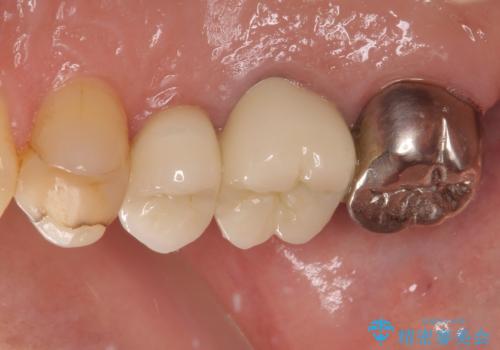

目立つ銀歯も根管治療を行い、その後2本の歯をオールセラミッククラウンにて補綴治療を行うこととしました。

大臼歯では、根管治療後にも痛みが残ってしまったため、外科的歯内療法(歯根端切除術)を適用しました。外科処置直後は腫れや痛みなどがありましたが、半年が経過し、痛みがなくなり、レントゲン写真上でも炎症の消退が認められました。